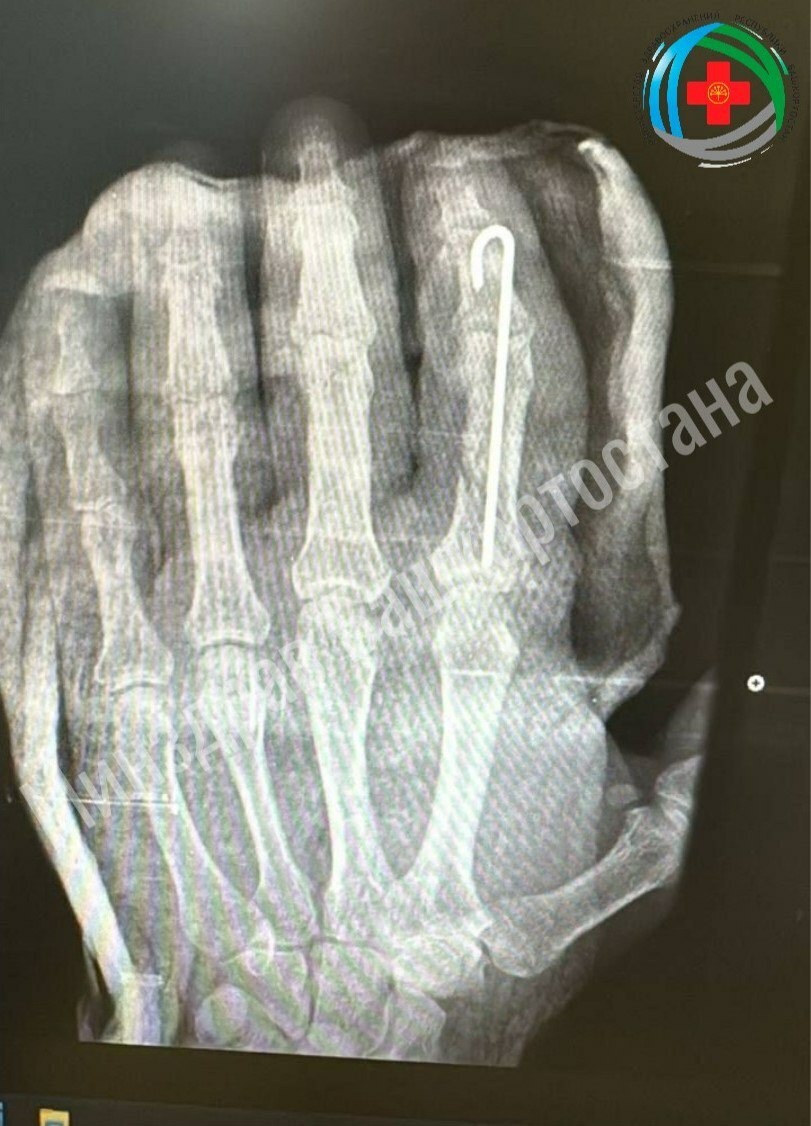

В Башкирии врачи пришили мужчине отрубленный палец

Экстренную операцию провели хирурги Благовещенской больницы, сообщает пресс-служба минздрава Башкирии. Житель Благовещенска отрубил себе палец сам, работая во дворе. Доктора провели ювелирную работу по его восстановлению, которая включала сшивание мельчайших сосудов для возобновления кровотока, точную фиксацию костей и реконструкцию мягких тканей.

Благодаря профессионализму медиков палец прижился. Сейчас пациент проходит восстановительное лечение, которое включает медикаментозную терапию, физиотерапию и лечебную физкультуру. Ожидается полное восстановление функций пальца после завершения реабилитации. Фото: минздрав РБ.